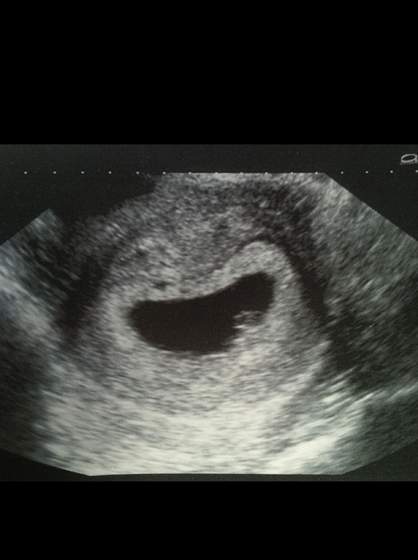

Ja po pierwszym usg :) wszystko pieknie, Fasolinka ma 7mm czyli odpowiada dokladnie moim 6tyg 3d :D

Widzielismy tez na ekranie pulsujace serduszko :)

Najpierw mialam robione usg przez brzuch, i pani juz mowila, ze chyba widzi serduszko, ale jeszcze zrobila mi dopochwowe, zeby sie upewnic i stwierdzila, ze wszystko jak na ten wiek ciazy wyglada perfekcyjnie, zarodek osadzony w prawidlowym miejscu, prawidlowy rozmiar, pulsujace serduszko

a oto Ktosiek: